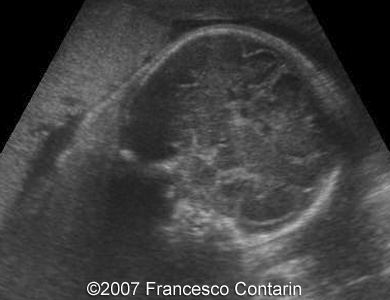

This is a 22-year-old woman (G4, P2) with unremarkable familiar history, referred to our hospital at 29 weeks of gestation due to a fetal ascites. There were no signs of maternal-fetal blood incompatibility. The ultrasound investigation revealed rhizomelia, postaxial polydactyly, small thorax, short ribs, ascites, increased abdominal biometric parameters, polyhydramnios. We supposed two diagnoses: Short rib-polydactyly syndrome versus Jeune syndrome (asphyxiating thoracic dystrophy).

Images 11, 12. 29th week of pregnancy -  coronal plane through normal fetal lips and nose (left); and coronal plane through the fetal skull - normal (right).

Images 13, 14. 29th week of pregnancy -  sagittal cranial plane - normal (left); and axial plane through the posterior fossa of the skull - normal cerebellum with transcerebellar diameter concordant with gestational age (right).